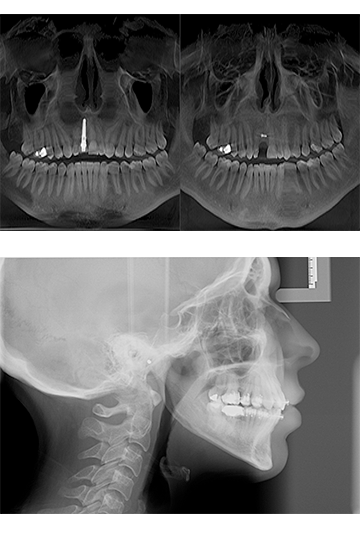

La radiología digital, cuya transmisión de imágenes a través de un sensor a la computadora desde el equipo de rayos X, permite administrar, visualizar, analizar imágenes radiológicas en una variedad de 256 tonos de gris.

La radiología computarizada permite obtener calidad, cantidad y variabilidad de datos porque cuenta con un sinnúmero de herramientas de análisis con las que usted puede explorar hasta elúltimo detalle para llegar a un diagnóstico preciso.

Todo esto nos permite afirmar que la radiología digital tiene un potencial irrefutable que hace posible que de una sóla imagen se pueda obtener información a detalle.

En 2003, el laboratorio de radiología diagnóstica en ortodoncia S.A. de C.V., pone a disposición de odontólogos y ortodoncistas el primer Orhtopanthomógrafo Digital, siendo los primeros en México en ofrecer tecnología de punta para sus consultorios y pacientes. Dicha innovación le permite a los especialistas contar con un sinnúmero de herramientas de diagnóstico y análisis.